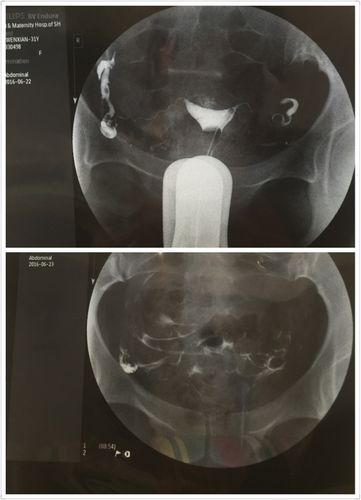

1.输卵管造影

(1)输卵管造影是通过导管注入造影剂,将造影剂送入宫腔,起到肉眼下端治疗疾病的作用。造影具有通液作用,造影后放置患处可以利用过氧化氢来形成凝胶,之后拆除胶体,达到诊断并辅助治疗的作用。

(2)造影具有镇静作用,造影具有良好的热性。造影有利于清楚造影组织的病变部位和病灶部位,便于医生调整治疗方案。造影可以直接反应细胞的病变和病变情况,从而达到确诊目的。